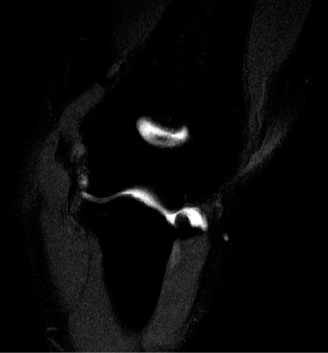

The patient undergoes conservative management consisting of rest, anti-inflammatory medications, and physical therapy. After six months, he is still not able to return to play and has progressively worsening symptoms with attempted throwing. He has a moderate elbow effusion as well as a 20-degree flexion contracture. An elbow MRI arthrogram is obtained and shown (Fig. 2–112). He elects to proceed with elbow arthroscopy. Intraoperative arthroscopic images are shown (Figs. 2–113 and 2–114).

Figure 2–112

Figure 2–113

Figure 2–114